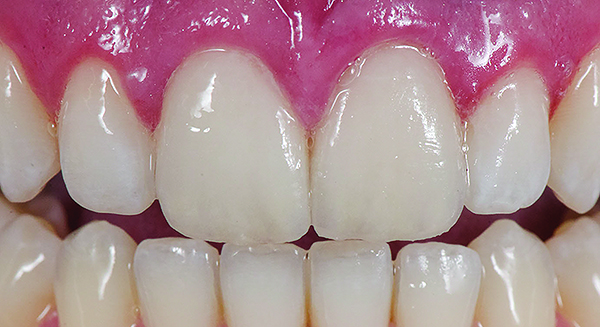

Class I (CL-I) powder and liquid porcelains are created from materials primarily containing silicon dioxide and possess a glassy matrix and varying amounts of a crystalline phase within the glassy matrix (eg, Creation Porcelain, Jensen Dental, www.jensendental.com; Ceramco 3, DENTSPLY International, www.dentsply.com; EX-3, Kuraray Noritake Dental, Inc, www.kuraraynoritake.com). The CL-1 group includes feldspathic porcelains, referred to as such because they were originally—and some continue to be—made from naturally occurring feldspars (ie, aluminosilicates composed of assorted quantities of potassium, sodium, barium, or calcium).9,17 Several feldspathic material options are available on the market today (eg, VITA VM 13, VITA Zahnfabrik, www.vita-zahnfabrik.com; Vintage Halo, Shofu, www.shofu.com) (Figure 1 through Figure 3).

CL-I materials are fabricated by hand (Figure 4); they are the most conservative and generally the most translucent ceramic materials, but they are also the weakest.9,10,18 The material’s high translucency and esthetics create the illusion of natural teeth.9 Powder/liquid porcelain materials are ideal for cases in which significant enamel remains and/or there is healthy tooth structure on the teeth (ie, 50% or more remaining enamel on the tooth, 50% or more of the bonded substrate is enamel, and 70% or more of the margin is in the enamel). Feldspathic porcelain restorations that are bonded to primarily enamel substrates have proven to be highly successful long term.19

Powder/liquid porcelains demonstrate high esthetics and workability, and because they can be layered very thinly and placed directly on the enamel, they are considered the most conservative of the metal-free ceramic classes.10 CL-I porcelains require a thickness of 0.2 mm to 0.3 mm for each shade change.20,21

This class of materials is generally indicated for anterior restorations, but can also be used for the occasional bicuspid and rare molar, providing all parameters are at a very low risk level (Figure 5 and Figure 6).

Figure 1 Preoperative, preparation, and final postoperative images of a 2-unit CL-I feldspathic veneer case.

Figure 1

Figure 2 Preoperative, preparation, and final postoperative images of a 2-unit CL-I feldspathic veneer case.

Figure 2

Figure 3 Preoperative, preparation, and final postoperative images of a 2-unit CL-I feldspathic veneer case.

Figure 3